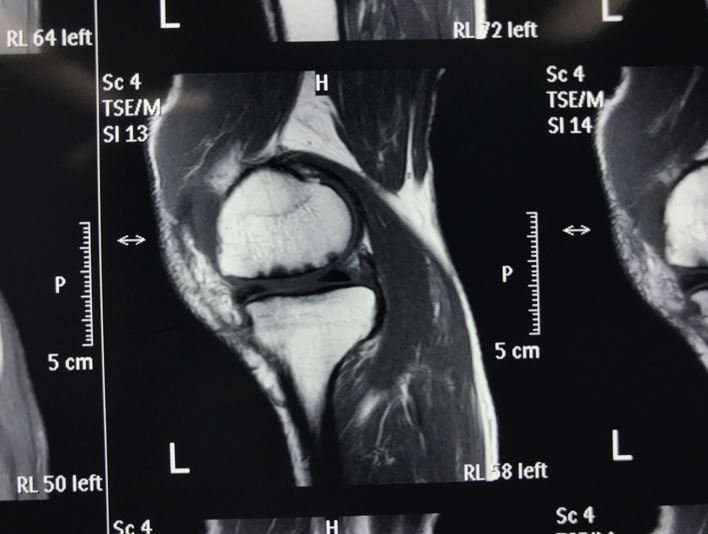

膝关节磁共振图

放射科–––核磁共振成像(mri)

核磁共振膝关节读片